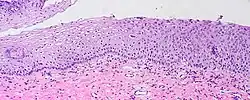

Visualization of koilocytes

Koilocytes can be visualized microscopically when tissue is collected, fixed, and stained. Though koilocytes can be found in lesions in a number of locations, cervical cytology samples, commonly known as Pap smears, frequently contain koilocytes.[6] In order to visualize koilocytes collected from the cervix, the tissue is stained with the Papanicolaou stain.[6] Another way koilocytes can be visualized is by fixation of tissue with formalin and staining with hematoxylin and eosin, commonly known as H&E.[6] These stains give the cytoplasm and nuclei of cells characteristic colors and allows for visualization of the nuclear enlargement and irregularity, hyperchromasia, and perinuclear halo that are typical of koilocytes.

In LSIL of the cervix, definitive koilocytes are present. In addition, squamous cells commonly display binucleation and mitoses are present, signifying increased cellular division.[8] However, these changes are primarily limited to upper cell layers in the epithelium, no mitoses are found higher than the lower one third of epithelium, and the basal layer of cells remains a discrete layer. This differentiates this lesion from high-grade squamous intraepithelial lesion (HSIL) of the cervix.[8]